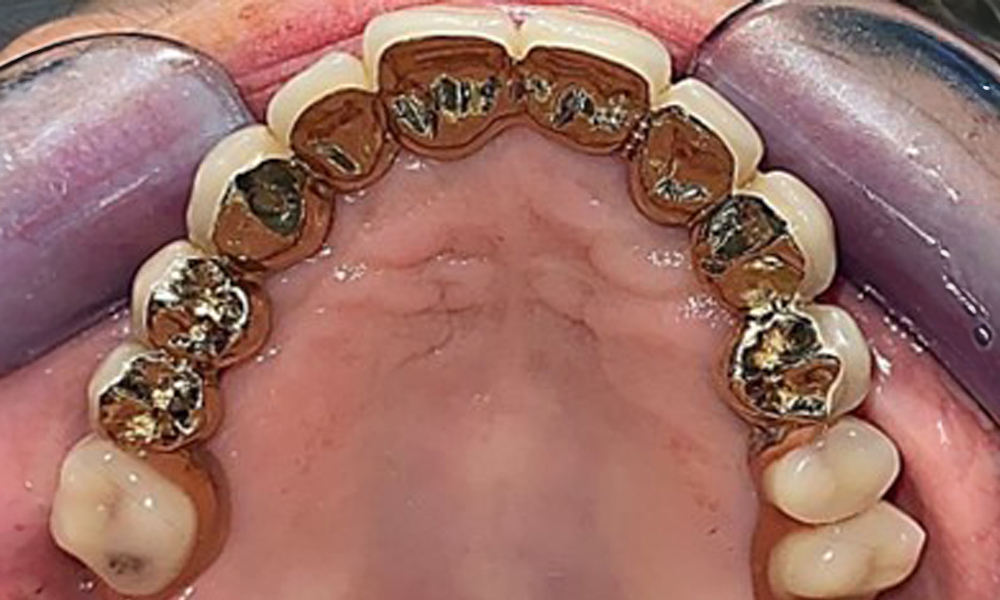

Okklusalansicht: Oberkiefer mit Zahn- und implantatgetragenen Teleskopen.

Abb. 2: Okklusalansicht: Oberkiefer mit Zahn- und implantatgetragenen Teleskopen.

Der dentale Befund stellt sich wie folgt dar: Kombinierte herausnehmbare Implantat- und zahngetragene Teleskoparbeit auf Implantaten 15, 13, 21, 23, 24, 25 und Zahn 11 (Abb. 1, Abb. 2, Abb. 3). Im Unterkiefer ist die Patientin mit einem festsitzenden Zahnersatz versorgt. 37–34 sowie 45–47 haben suffiziente Brücken (Abb. 4). Kronenränder sind intakt, aktive kariöse Läsionen sind nicht vorhanden. An Zahn 43 zeigt sich eine Compositefüllung mit Randspalt. Im Unterkiefer liegen Rezessionen mit freiliegender Wurzeloberfläche zwischen 1 – 3 mm vor. Dies trifft auch für 11 zu.

Die Patientin wurde vor über 25 Jahren mit einer kombinierten herausnehmbare Implantat-Teleskopprothese im Oberkiefer versorgt (Abb. 1, Abb. 2, Abb. 3) und ist sehr glücklich über ihren Zahnersatz. Im Unterkiefer hat die Patientin einen suffizienten festsitzenden Zahnersatz. (Abb. 4)